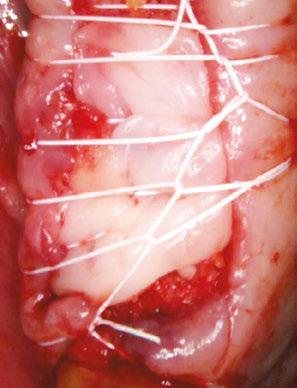

molars in January 2019. The past medical history was significant for cystic fibrosis and depression. He had an allergy to sulfa medications and was taking the following medications: Pulmozyme® (dornase alpha), testosterone, prednisone, and nifedipine. The patient presented with a chief complaint of “I didn’t think I was going to live this long with cystic fibrosis, but I did, and now I am ready to take care of my needs.” The clinical examination was significant for a grossly carious dentition in need of repair (Figure 1). After reviewing several options, it was decided to extract the non-restorable left maxillary first, second, and third molars and to restore the maxillary left first and second molars with fixed implant-retained restorations. With potential healing concerns secondary to his cystic fibrosis, the addition of platelet-rich fibrin (PRF) was discussed. The patient was taken to the surgical operatory where the blood pressure was taken, a pulse oximeter placed, and an IV was started using a 21-gauge butterfly catheter in the right antecubital fossa. PRF protocol was followed using Intraspin® centrifuge (BioHorizons; Birmingham, Alabama), and anesthesia was maintained thereafter using a balance technique. Maxillary left first, second, and third molars were surgically removed, and the resulting extraction sockets were curetted free of granulation tissue. PRF clots and membranes were prepared as described by Choukroun, et al.15 The PRF was mixed 50/50 with MinerOss® mineralized allograft cancellous bone particles (BioHorizons; Birmingham, Alabama) resulting in a “sticky bone preparation” that was placed in the maxillary left first and second molar sockets (Figure 2). Two PRF membranes were placed across the extraction sites (Figure 3), and 3-0 PTFE interrupted sutures were placed affording good wound apposition (Figure 4). Adequate soft tissue healing was observed at a 3-week postoperative check.

Figure 5: Panoramic radiograph taken after healing of the grafted areas prior to implant placement Figure 6: CBCT taken after healing of the grafted areas prior to implant placement Figure 2: Placing the PRF and cortical cancellous bone preparation “sticky bone” into the extraction sockets Figures 3 and 4: 3. Double-layer PRF membrane placed underneath the buccal and palatal flaps prior to closure. 4. 3-0 PTFE suture used to provide closure of the buccal and palatal flaps and stability of the PRF membrane. Notice here primary closure is not necessary. This technique will provide a large band of keratinized tissue for use during implant placement